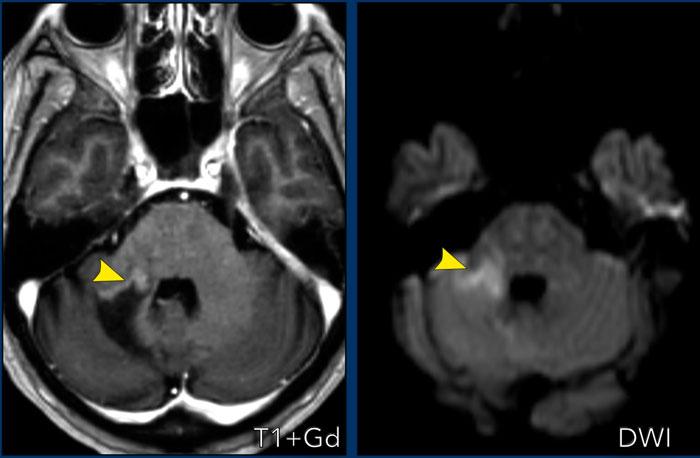

Toxoplasmosis

Các hình ảnh này của bệnh nhân nữ 50 tuổi, nhập viện với triệu chứng liệt nửa người bên trái.

Tiền sử bệnh không có gì đặc biệt.

Hình ảnh

Ghi nhận một tổn thương ngấm thuốc dạng viền ở thùy trán phải.

Không có hạn chế khuếch tán ở trung tâm, nhưng có dấu hiệu bia lệch tâm (eccentric target sign).

Dấu hiệu bia này gợi ý mạnh cho chẩn đoán toxoplasmosis não.

Dấu hiệu này được cho là biểu hiện của các mạch máu viêm ngấm thuốc nằm bên trong khoang áp xe.

Đây là trường hợp tương tự của bệnh nhân nữ 34 tuổi, nhập viện với triệu chứng động kinh.

Ghi nhận một tổn thương ngấm thuốc dạng viền ở thùy trán trái với dấu hiệu bia và hạn chế khuếch tán dạng viền.

Lưu ý thêm giảm tín hiệu trên chuỗi xung T2W và FLAIR.

Chẩn đoán cuối cùng: toxoplasmosis.

Trong khi các tác nhân vi khuẩn gây áp xe điển hình thường gây hạn chế khuếch tán ở trung tâm, các tác nhân không điển hình như nấm và toxoplasmosis thì không, khiến chẩn đoán áp xe não trở nên khó khăn hơn.

Dấu hiệu bia lệch tâm như trong trường hợp này rất có giá trị cho chẩn đoán.